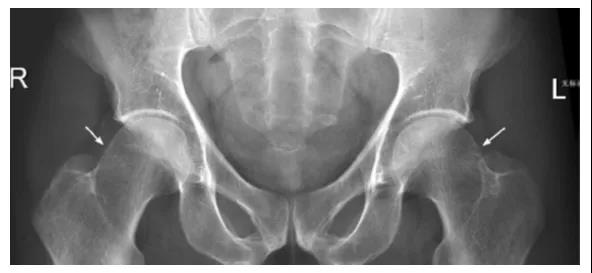

FAI影像学检查前后位片:可见股骨头不同程度的手枪柄样畸形侧位片: 观股骨头颈交界处骨性隆起;CE角﹥40°;髋臼后倾畸形;股骨颈的囊性变

FAI:齿轮型(cam-type )影像:股骨头、颈间的凹陷不足,可伴局部的骨质增生、硬化、囊变部位:前外股骨头、颈交界区

FAI:螯钳型(pincer-type)横断面显示髋臼后倾尤其是上1/3的后倾